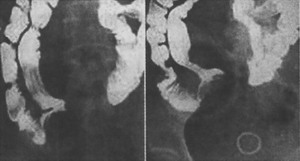

小腸鋇餐的常規檢查陽性率低。小腸灌鋇法可提高檢出率,顯示充盈缺損和黏膜潰瘍等。選擇性腹腔或腸系膜上動脈造影在動脈相時可見到較多血管進入瘤體,實質相時瘤體染色;合併出血時可見造影劑進入腸道。腹部b超往往因腸腔氣體干擾而難以發現腫瘤。ct常能顯示腫瘤的大致位置,大小、形態和與腸壁的關係等。當病者有出血而各種檢查未能確定診斷時,尚可用一簡單的吞線檢查,有時可有助於明確出血部位。用白色棉線末端系一顆粒糖吞下,留置一天后取出檢查染血部與門齒的距離以推測病部。以後可再根據推測部位再作小腸x線檢查或直接剖腹探查。